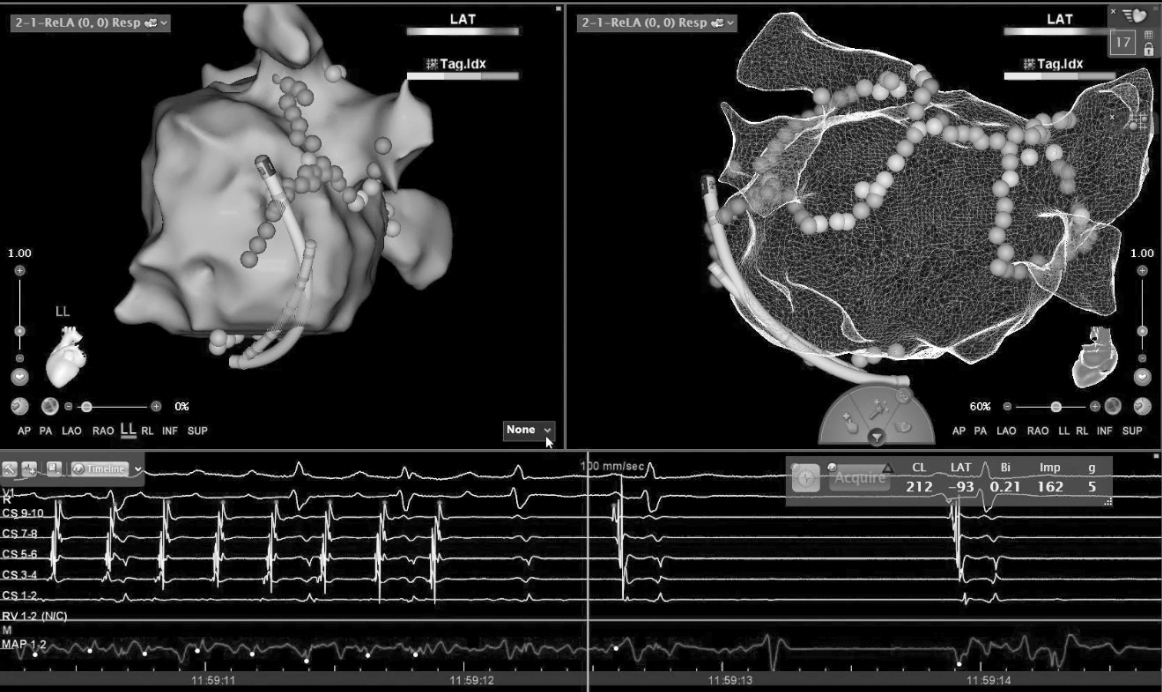

STSF高功率房颤射频消融

项目简介:STSF作为一款头端56孔盐水灌注的压力消融导管可以同时优化射频消融的功率,和减少整体灌注量,对于提高肺静脉的单圈隔离率(最基础的心房颤动治疗策略)有着巨大帮助,高功率的消融模式,可以增强消融的连续和透壁性,增加了手术有效性的同时,缩短手术时间。而进一步降低灌注量又可以大幅度提高心衰和其他合并症患者的手术并发症概率,提高手术效率。